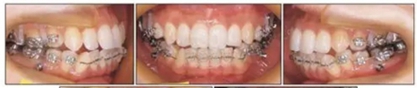

患者在9-15歲間接受過拔除雙側(cè)上頜第一前磨牙的正畸治療。在此期間,患者有雙側(cè)顳下頜關(guān)節(jié)彈響癥狀。在28歲時,發(fā)展出牙關(guān)緊閉和關(guān)節(jié)區(qū)疼痛,并于本院的口腔頜面外科求治??谇煌饪漆t(yī)生診斷顳下頜關(guān)節(jié)內(nèi)紊亂和骨關(guān)節(jié)炎并進行物理治療和合墊治療以緩解疼痛。在此期間未發(fā)現(xiàn)髁突形態(tài)改變(Figure 1A)。

然而,患者的關(guān)節(jié)癥狀沒有改善甚至有惡化。并且,在左側(cè)髁突出現(xiàn)了骨刺樣退行性改變(Figure 2)。因此,進行了視覺引導(dǎo)下的顳下頜關(guān)節(jié)沖洗和開放手術(shù),此后患者癥狀有改善。然而,雙側(cè)髁突的退行性變導(dǎo)致了開合和下頜順時針旋轉(zhuǎn)。對開合和髁突情況觀察一年以排除有害改變(Figure 1B)。而后,患者被介紹到正畸科糾正開合。

面部照片顯示,患者為凸面型,鼻唇時頦肌緊張(Figure 3)。口內(nèi)檢查顯示雙側(cè)第二前磨牙間開合(Figures3 and 4)。覆合覆蓋分別為-3.5mm和+1.2mm。正面觀,上下牙列中線與面部中線一致。雙側(cè)磨牙II類關(guān)系,下前牙區(qū)中度擁擠。

在上下頜安裝橫腭桿和舌弓以準備磨牙壓低。在上下頜雙側(cè)安裝第二前磨牙到第二磨牙片斷弓。

局麻下于植入支抗釘,上頜植入部位在雙側(cè)第二前磨牙和第一磨牙間以及雙側(cè)第一磨牙和第二磨牙間頰側(cè)牙槽骨,下頜植入部位在雙側(cè)第二前磨牙和第一磨牙間間頰側(cè)牙槽骨。植入四周后,用鏈圈連接支抗釘和片斷弓進行磨牙壓低。11個月后,覆合從-3.5mm增大到0.5mm (Figure 6)。在此期間沒有出現(xiàn)顳下頜關(guān)節(jié)癥狀。覆合覆蓋分別為0.5mm和3.5mm。頭測分析顯示有下頜骨旋轉(zhuǎn)(FMA, 46.7°to 44.0°)。移除下頜支抗釘和舌弓。